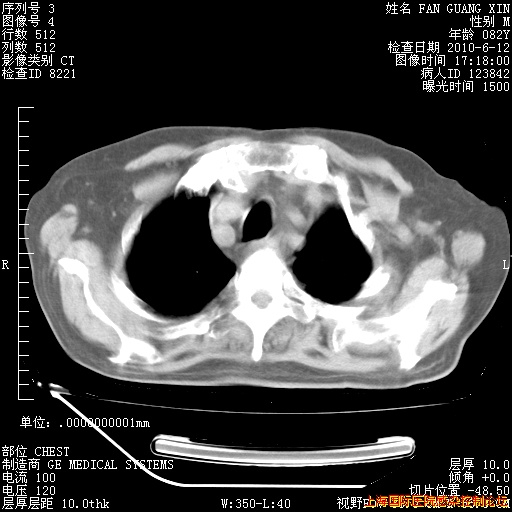

补发6月12日肺部CT肺窗

6月12日肺窗

6月12日纵膈窗